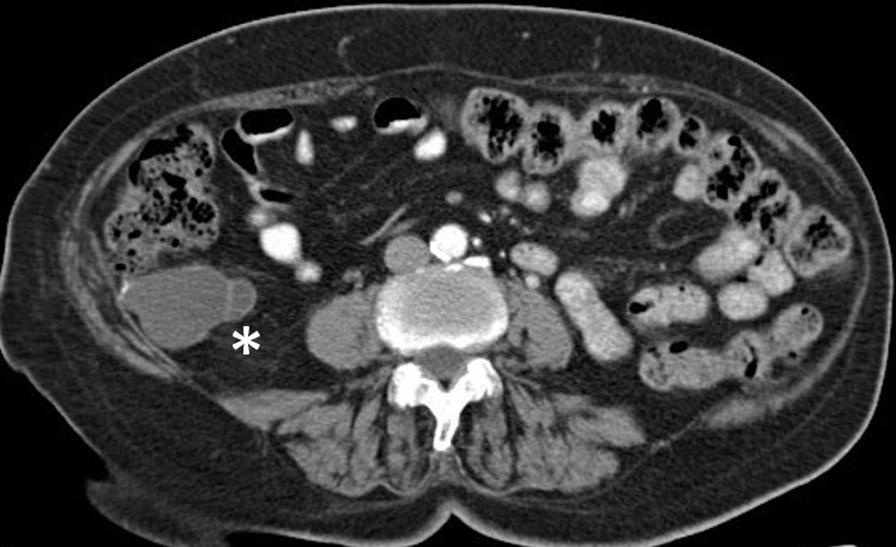

Twenty-nine patients with a diagnosis of appendiceal neoplasm were identified, and 24 corresponded to neoplastic appendiceal mucinous lesions (85.7%). The average age was 59.7 ± 17.6 years. Most patients were women (15 cases; 62.5%). Most of them presented with chronic abdominal pain (37.5%), and the diagnosis was performed by computed tomography (CT) (50%). The treatment was surgical in all cases. The surgical technique depended on the findings and histology of the tumour.